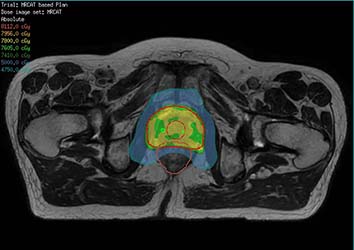

Ya sea para la radioterapia (RT) con haces externos o braquiterapia, la integración de la adquisición de imágenes de la RM en la planificación basada en la TC puede aprovechar el poder de la RMN y transformar el manejo de los pacientes. Gracias al contraste excelente del tejido blando que ofrece la RMN, se pueden observar claramente el tumor y los órganos en riesgo. De modo que puede respaldar la precisión en la delineación y el diseño de los mejores planes de tratamiento posibles. Imagen de cortesía del sistema William Beaumont Health System, Detroit, EE.UU.

Today, MR has even more to offer radiation therapy treatment planning. Innovative MR-only simulation by Philips helps you rely on MR as a primary imaging modality for planning the treatment of prostate cancer patients.

Available as a plug-in extension to the Ingenia MR-RT, MR-only sim provides the excellent soft-tissue contrast you trust for target delineation – plus density information for dose calculations. And it’s designed for your workflow. Fast scanning protocols and embedded post-processing steps generate MRCAT (MR for Calculating ATtenuation) images on the MR console in just a few minutes with the density information you’d expect from CT.